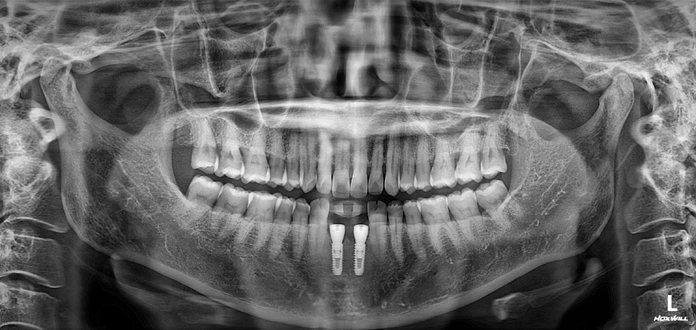

Before

After